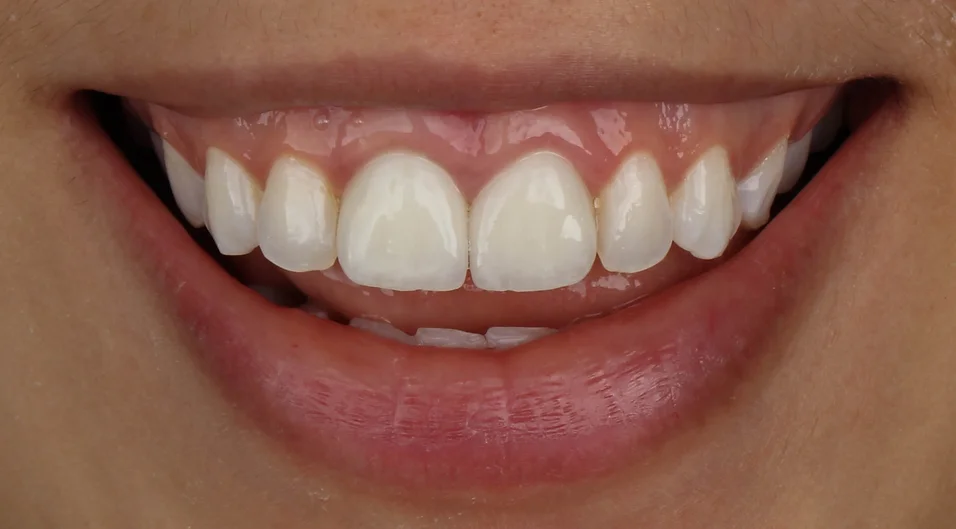

Realizamos então a exodontia do incisivo central superior direito, seguido de implante, enxerto 100% com biomaterial, provisório imediato e posterior troca da faceta do incisivo central superior esquerdo. A maior preocupação era utilizar uma técnica cirúrgica que mantivesse o alinhamento da gengiva com os dentes vizinhos e uma reabilitação protética que escondesse o implante e a faceta do dente vizinho no conjunto do sorriso.